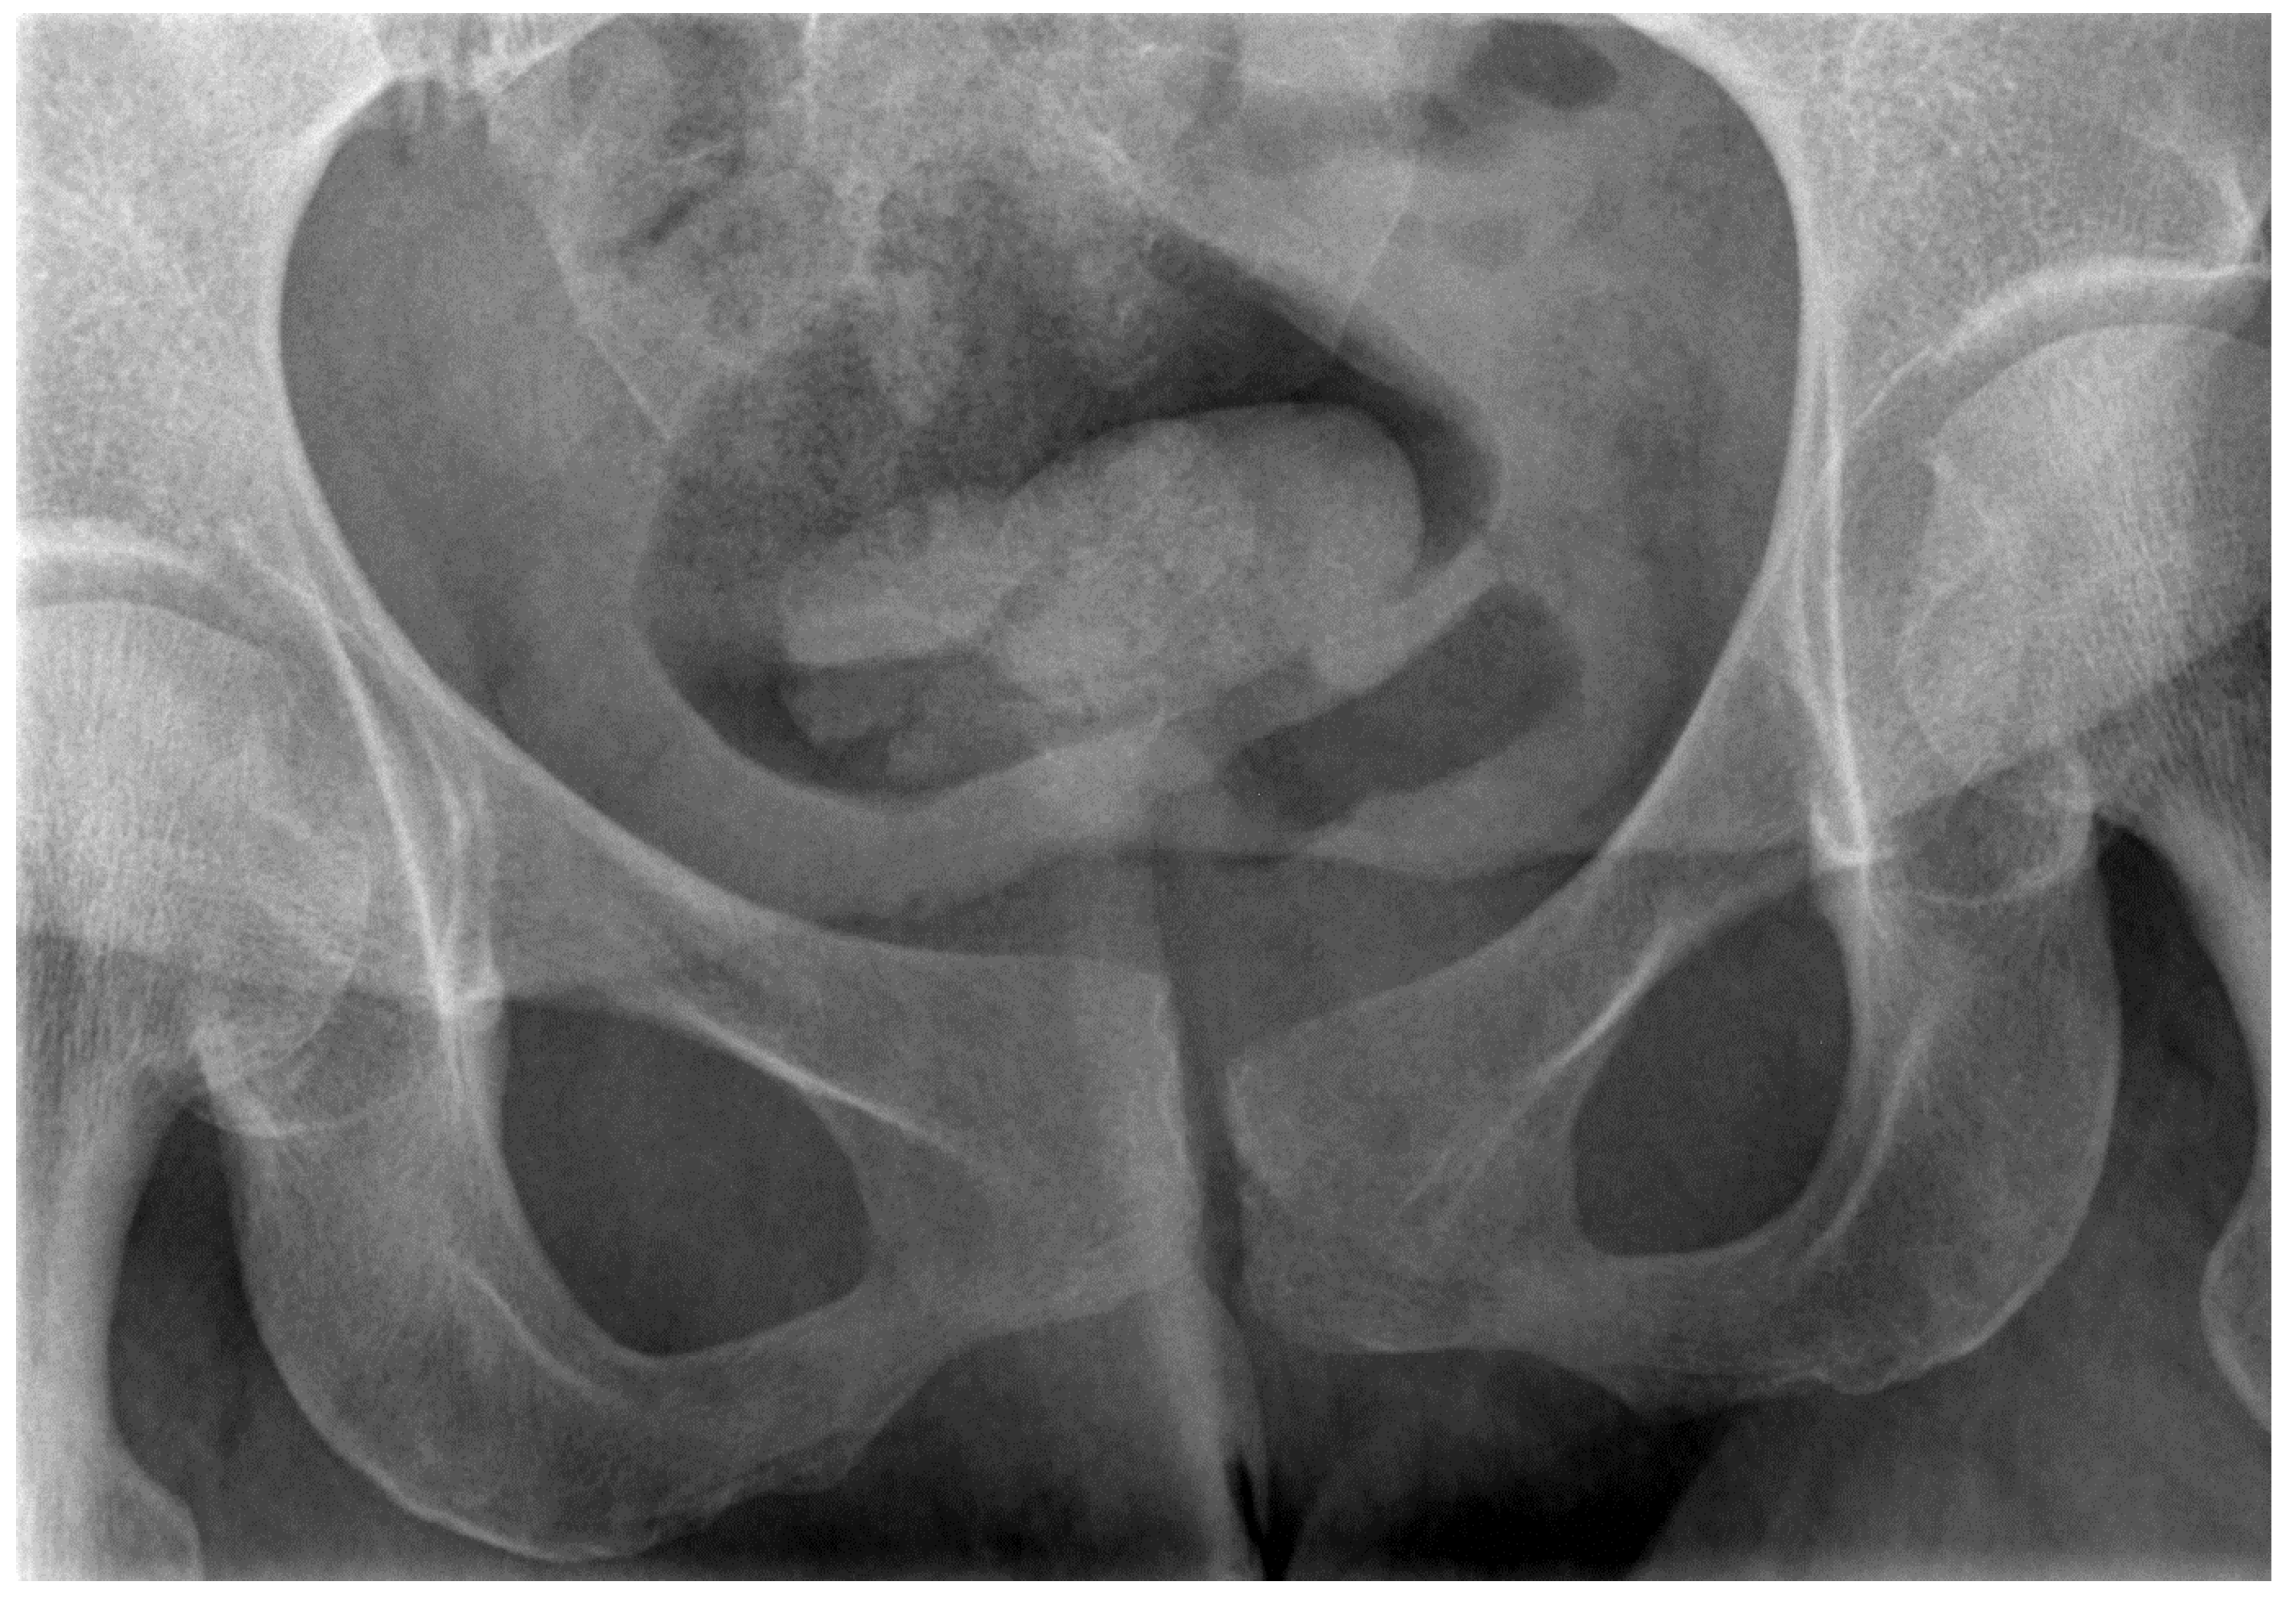

- Garras, D.N.; Carothers, J.T.; Olson, S.A. Single-leg-stance (flamingo) radiographs to assess pelvic instability: How much motion is normal? J. Bone Joint Surg. Am. 2008, 90, 2114–2118. [Google Scholar] [CrossRef] [PubMed]

- Van Zwienen, C.M.; Van den Bosch, E.W.; Snijders, C.J.; Van Vugt, A.B. Triple pelvic ring fixation in patients with severe pregnancy-related low back and pelvic pain. Spine 2004, 29, 478–484. [Google Scholar] [CrossRef] [PubMed]